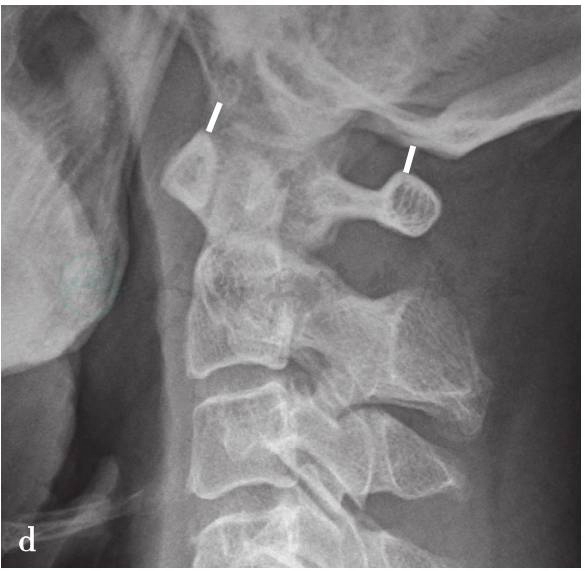

(4)Kaufman法:

枕骨髁与寰椎上关节面的距离,儿童正常小于5mm,大于此值为异常(图4d)。

图4

a.寰枕关节脱位X线测量方法(BDT法);b.寰枕关节脱位X线测量方法(Power法);c.寰枕关节脱位X线测量方法(Dublin法);d.寰枕关节脱位X线测量方法(Kaufman法);e.寰枕关节脱位X线测量方法(X线法);f.寰枕关节脱位X线测量方法(BAI-BDI法)